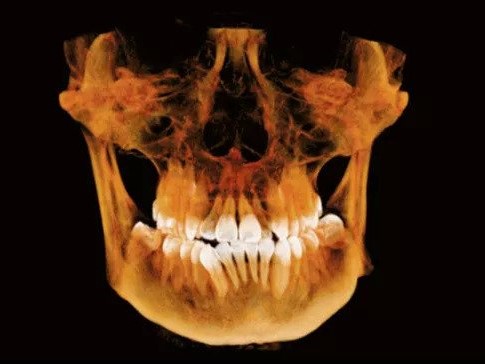

Stomatologia jak żaden inny dział medycyny na co dzień i powszechnie wykorzystuje badania radiologiczne w procesie diagnostyki i leczenia. W ciągu ostatnich lat w dziedzinie radiologii stomatologicznej doszło do radykalnych zmian i unowocześnień. Konwencjonalną radiologię analogową zastąpiły dużo sprawniejsze i doskonalsze a także przyjazne dla pacjenta ( mniejsza dawka promieniowania) systemy radiografii cyfrowej. Obecnie powszechnie wykonujemy cyfrowe zdjęcia rtg pojedynczych zębów a także cyfrowe zdjęcia panoramiczne i telerentgenogramy. Są one dostępne do obejrzenia i obróbki graficznej w ciągu kilku sekund po wykonaniu badania, a obraz takiego badania można przesłać np. mailem. Najnowszym osiągnięciem radiologii stomatologicznej jest badanie z zastosowaniem tomografii wolumetrycznej CBCT. Badanie to pozwala na doskonałej jakości przestrzenne (3D) obrazowanie struktur twarzoczaszki co pozwala na bardzo precyzyjne postawienie diagnozy, zaplanowanie leczenia i kontrolę jego efektów.

| Tomografia szczęki lub żuchwy (1 łuk) | 250 |

| Tomografia szczęki i żuchwy | 300 |